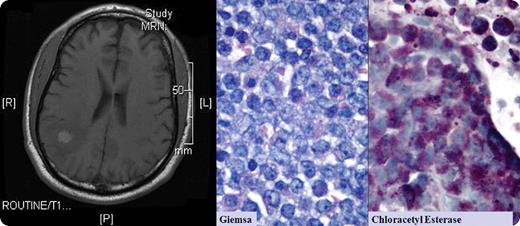

A 56-year-old man had a history of acute promyelocytic leukemia and had been in remission for 2 years. He developed the new onset of seizures. Brain MRI showed 2 well-circumscribed right parietal lobe lesions (one lesion shown above). Spinal fluid cytology was negative for malignant cells. Bone marrow aspiration and biopsy were negative. The neurosurgeon resected these lesions that were within brain tissue and distinct from the meninges. Microscopic review revealed an infiltrate of immature cells, CD10- and CD117-positive, and containing granules that appeared as promyelocytes.

Granulocytic sarcomas are rare collections of acute leukemic cells that can occur in any soft tissue area, including bone, skin, lymph nodes, breast, ovary, meninges, orbit, and optic nerve. In early reports, they were known as chloromas, because of their rich myeloperoxidase content that appeared green. Granulocytic sarcomas appear in individuals who have normal marrows. They usually precede marrow involvement by acute leukemia or chronic myelogenous leukemia by months to years.

After the neurosurgical procedure, the patient received localized CNS radiation. Three months later, a repeat bone marrow aspiration showed near-total replacement with promyelocytes. He was given aggressive chemotherapy followed by consolidation with all-trans retinoic acid and arsenic trioxide. Four months later, there was no evidence of recurrence, either on MRI or in the marrow.